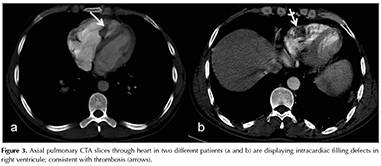

Intra-cardiac filling defects consistent with thrombosis was localized in the right atrium in three of patients and confirmed by echocardiography, with a maximum diameter of 24 mm, 13 mm and 19 mm, respectively.

Heart chambers and pericardia are other sites of involvement in BD. The site of thrombosis is frequently the right ventricle followed by the right atrium in BD (11). Among our patients, CT demonstrated intra-cardiac filling defects consistent with thrombosis adhering to the right ventricle's anterior and lateral walls in 3 patients which had PAAs also (Figure 3). The thrombosis nearly regressed completely, except for minimal focal thickening. Echocardiography confirmed the presence and site of the localization of thrombosis in all of them. Left ventricular involvement is rare and reported only in a few cases in the literature (20). It should be noted that majority (3/4) of the patients with PAA had concomitant thrombosis the right cardiac chambers those could be seen on non gated chest scans in our study. Thus patients with PAA should be examined for intracardiac thrombosis particularly in the right ventricle.